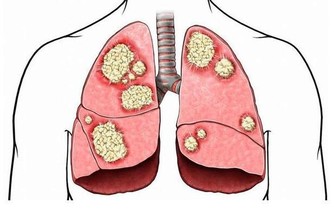

維生素在我們整個人體的免疫系統中發揮著非常重要的作用,身體抵抗外來侵害時各類免疫細胞的數量、活力都和維生素有關。

也可以多食用富含維生素C的新鮮蔬菜和水果,例如獼猴桃、橙子。為使呼吸道黏膜經常保持濕潤,還要補充維生素A,最佳來源是茴香、胡蘿蔔和甘藍。此外,經常吃一小撮核桃仁或葵瓜子,它們富含維生素E。